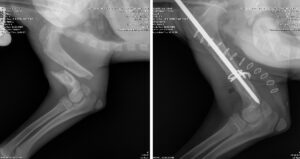

hmh-yukon-xray-pre-and-post-op-112025 By mmyles|2025-12-12T11:40:07-04:00December 12th, 2025| Share This: FacebookXEmail